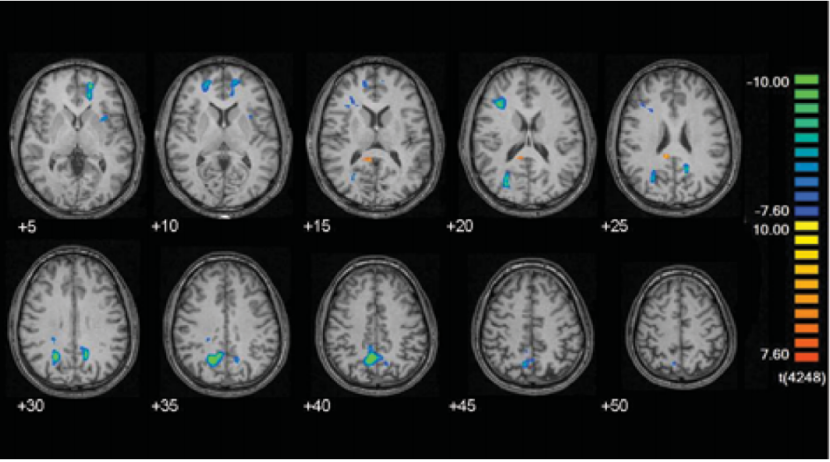

研究结果发现,在正念冥想时,与控制任务相比,观察到参与者大脑与内感觉相关的中线皮质结构的信号显著减少,这些大脑结构包括双侧前岛、左侧腹前扣带回、右侧前额叶内侧和双侧楔前叶,而右侧扣带回后部信号明显增强。

(在FMRI研究中观察到,正念任务状态和对照任务相比,参与者大脑中与内感相关的中线皮质结构的信号显著减少,右侧扣带回后部信号明显增强)